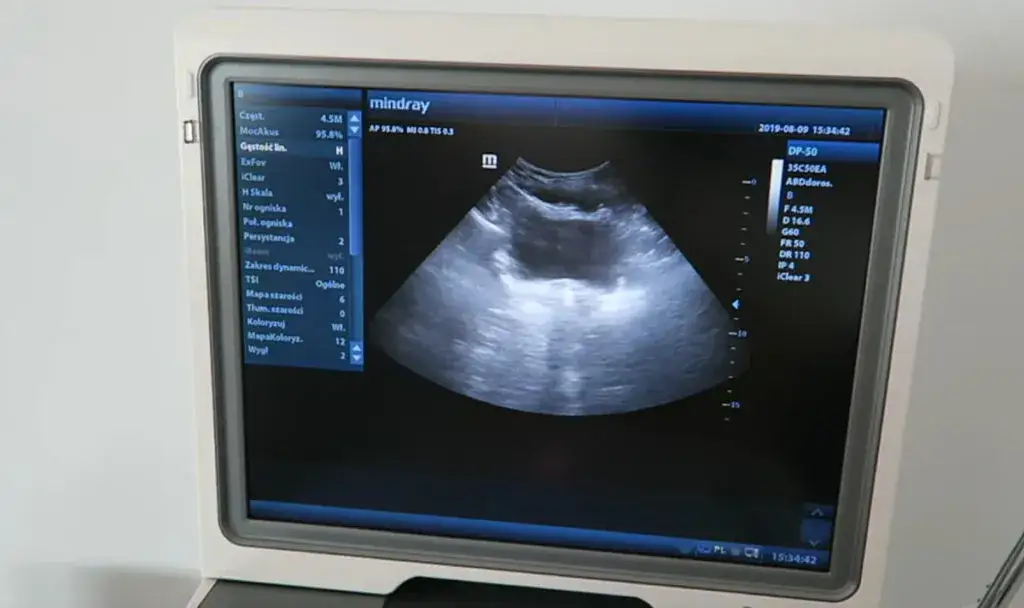

USG w fizjoterapii uroginekologicznej: Zobacz na własne oczy, jak pracują Twoje mięśnie.

Coraz częściej w fizjoterapii uroginekologicznej wykorzystujemy nowoczesne narzędzia diagnostyczne, takie jak ultrasonografia (USG). Może to być USG przezbrzuszne lub przezpochwowe, w zależności od potrzeb. USG pozwala mi na ocenę funkcji mięśni dna miednicy i pęcherza w czasie rzeczywistym. To niezwykle cenne narzędzie, ponieważ możesz na własne oczy zobaczyć na ekranie, jak pracują Twoje mięśnie, gdy je napinasz lub rozluźniasz. Taka wizualizacja znacząco ułatwia naukę prawidłowej aktywacji mięśni dna miednicy, zwiększa świadomość ciała i motywuje do dalszej pracy. To naprawdę fascynujące, gdy pacjentka po raz pierwszy widzi, jak jej mięśnie reagują na polecenia!